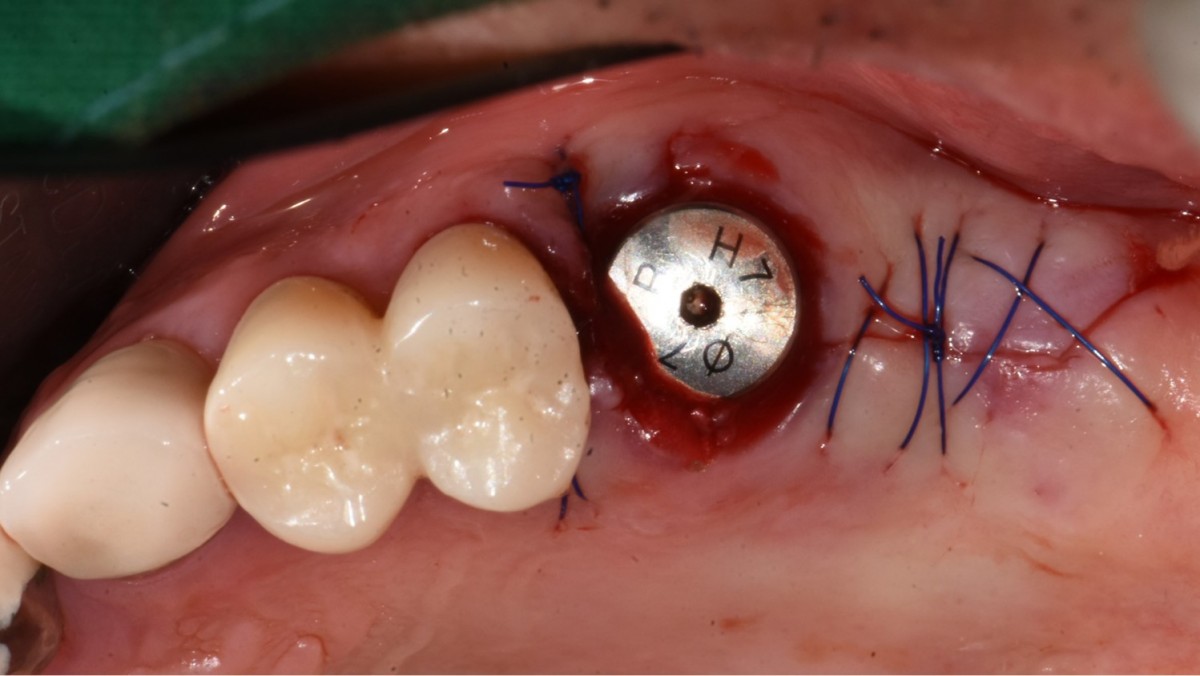

▲2 implants were placed. ArumDentistry NB1 5*10 (30Ncm) in the 1st molar and 5*10 (10Ncm) in the 2nd molar.

▲HA was inserted into the membrane with a hole in the middle and then inserted into the place where the Direction Pin was pulled out